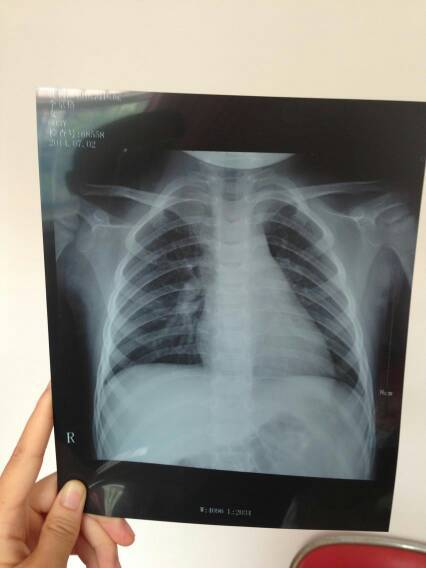

孩子的刚拍的片子能看出严重吗?需要怎样治疗,经常半夜会咳嗽 孩子的刚拍的片子能看出严重吗?需要怎样治疗,经常半夜会咳嗽。 点击展开 聽天使在唱歌ζ 2014-07-03 15:47 为您推荐: 其他回答 你好,还有一张纸张上面有写着临床的结果,你可以拿给医生看的,咳嗽的话怕是肺炎的。 我是猫咪8 2014-07-05 10:53 相关问题 小孩咳嗽十几天了,最初几天还发烧,现在不烧了,今天拍片子医生说是肺炎 刚出生的宝宝42天有点咳嗽去医院看了 拍了片子是没问题的 可是医生还是让我宝宝住院 还要让宝宝一人住 宝宝下半夜和早上醒来有点咳嗽 白天不怎么咳怎么回事?怎么治疗?能不吃药有什么好办法,有什么偏方吗?